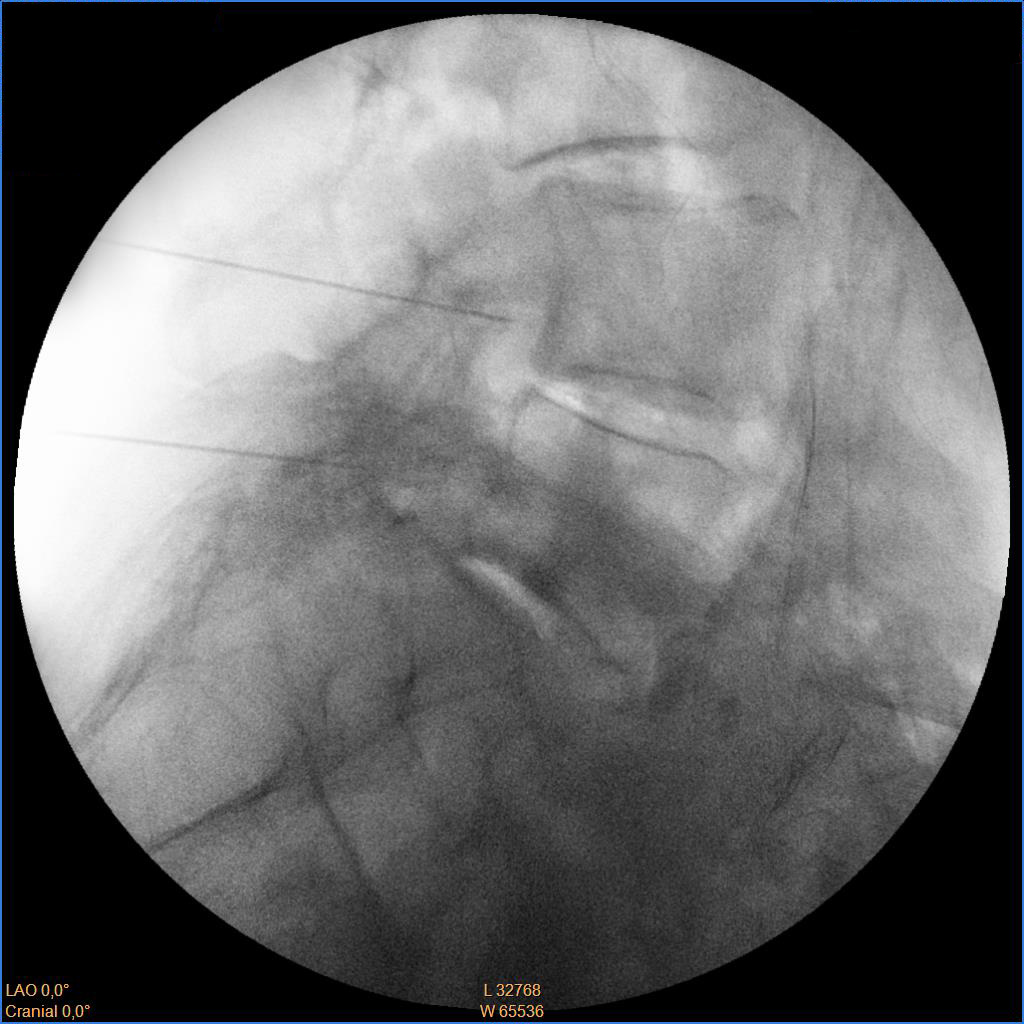

Ασθενής με σπονδυλαρθρίτιδα και 2 δισκοκήλες

Ασθενής 86 ετών με έντονο άλγος οσφύος, αντανάκλαση στο κάτω άκρο και αιμωδίες αριστερού άκρου ποδός απο 2μήνου λόγω σπονδυλαρθρίτιδας και 2 δισκοκηλών σε 2 επίπεδα. Με τοπική αναισθησία τοποθέτηση 2 βελόνων.  Έλεγχος σωστής τοποθέτησης με χρήση σκιαστικού και εισαγωγή μείγματος αναλγητικών. Άμεση ανακούφιση με αποτέλεσμα που διατηρείται 1.5 χρόνο μετά.